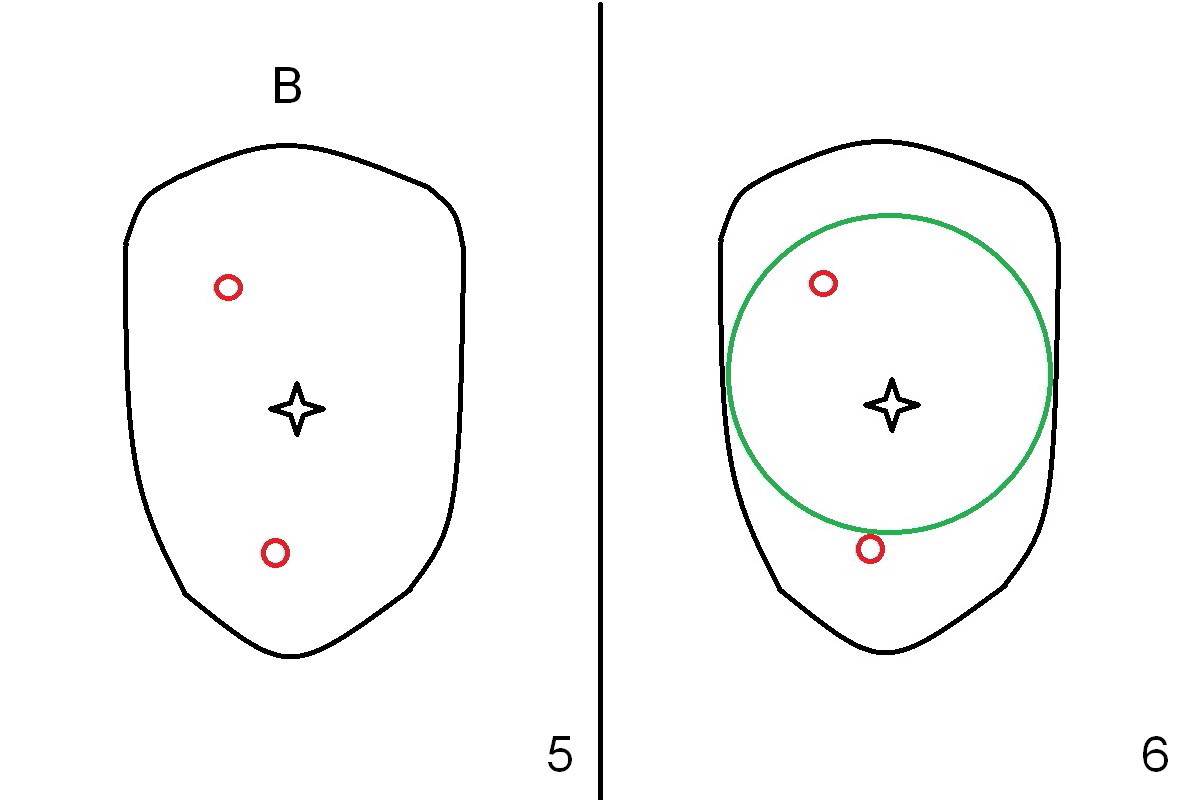

When the tooth is extracted, there is abundant granulation tissue in the socket. There is a perforation in the middle of the socket (Fig.5 (occlusal view of the socket) black star). A 2 mm osteotome is used to create an osteotomy palatally or buccally (Fig.5 red circles). The bone is less than 1 mm. As expected, the palatal wall is low. It appears that socket preservation is the treatment option. After placement of Osteotape in the bottom and palatal wall of the socket, allograft mixed with Osteogen is placed. The graft is covered by a 6-month collagen membrane, which is sutured in place. Implant placement is scheduled in 4-6 months. Although this is an acceptable treatment modality, it is not the best.

A large implant is place so that the mesiodistal dimension of the socket is obliterated by the implant (Fig.6 green circle). The buccal (Fib.5 B) and palatal gaps are filled with bone graft. It appears that either tapered (Fig4) or cylindrical (Fig.7) implant should be able to occupy the socket and obtain primary stability without perforating the sinus floor.